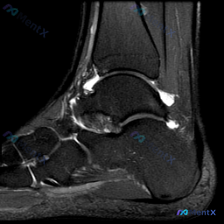

这是一份踝关节矢状位T2加权MRI图像,图像质量好,信噪比高,解剖结构清晰,涵盖了胫骨远端、距骨、跟骨、足舟骨、骰骨及部分跖骨基底部,胫距关节、距下关节、窦跗管、跟腱等关键结构都清晰显示。

- 关节与滑膜:胫距关节前、后隐窝都可见明显T2高信号,提示关节腔积液;距下关节间隙后部也可见积液;重点是窦跗管区域可见明显混杂T2高信号影,局部结构显示不清,有软组织信号增生填充

四、关键线索拆解——不要忽略窦跗管的异常

这份病例最容易踩坑的地方就是:只盯着软骨异常和关节积液,漏掉了窦跗管区域这个独立的显著异常。如果用单纯软骨损伤/骨关节炎来解释,完全没法解释这里的软组织增生,所以我们必须把鉴别方向扩展,用一元论来解释所有表现:

- 色素沉着绒毛结节性滑膜炎(PVNS):这是滑膜增生性疾病,好发于关节、腱鞘,窦跗管本身就有滑膜组织,典型表现就是滑膜增生,可伴随积液,早期或者部分亚型T2可以表现为混杂高信号,完全能解释这份影像的所有发现,概率最高